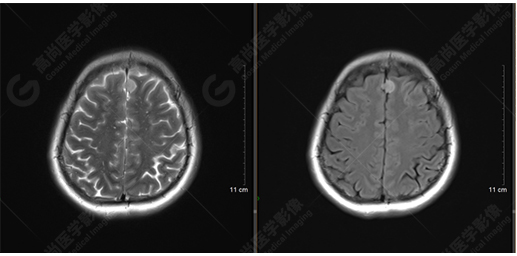

T2WI及FLAIR序列

橋腦見(jiàn)一類圓形異常信號(hào)影,直徑約1.3cm,呈T1WI稍高信號(hào),T2WI及FLAIR序列高信號(hào),其內(nèi)見(jiàn)高低信號(hào)分層,增強(qiáng)后無(wú)明顯強(qiáng)化。大腦鐮前部旁見(jiàn)兩個(gè)結(jié)節(jié)影,較大者直徑約1.4cm,呈各序列等信號(hào),增強(qiáng)后呈均勻明顯強(qiáng)化,鄰近大腦鐮增厚、強(qiáng)化。右側(cè)額葉腦白質(zhì)內(nèi)見(jiàn)一斑點(diǎn)狀等T1長(zhǎng)T2信號(hào)影,F(xiàn)LAIR序列呈高信號(hào),增強(qiáng)后無(wú)強(qiáng)化;余腦實(shí)質(zhì)內(nèi)未見(jiàn)局灶性信號(hào)異常,增強(qiáng)后未見(jiàn)異常強(qiáng)化。各腦室、腦池大小、形態(tài)均正常,中線結(jié)構(gòu)居中,幕下小腦無(wú)異常。矢狀面示垂體大小形態(tài)正常,未見(jiàn)局灶性信號(hào)異常。